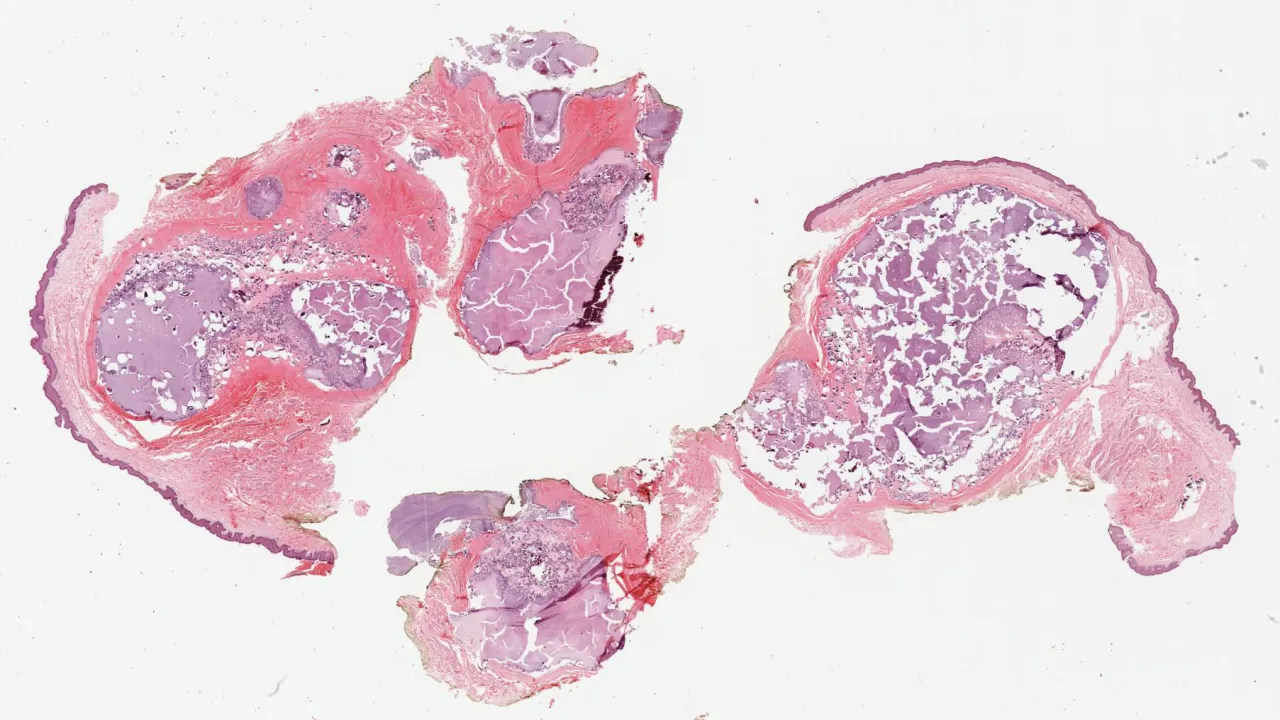

Testis, Mixed germ cell tumour, H&E stain